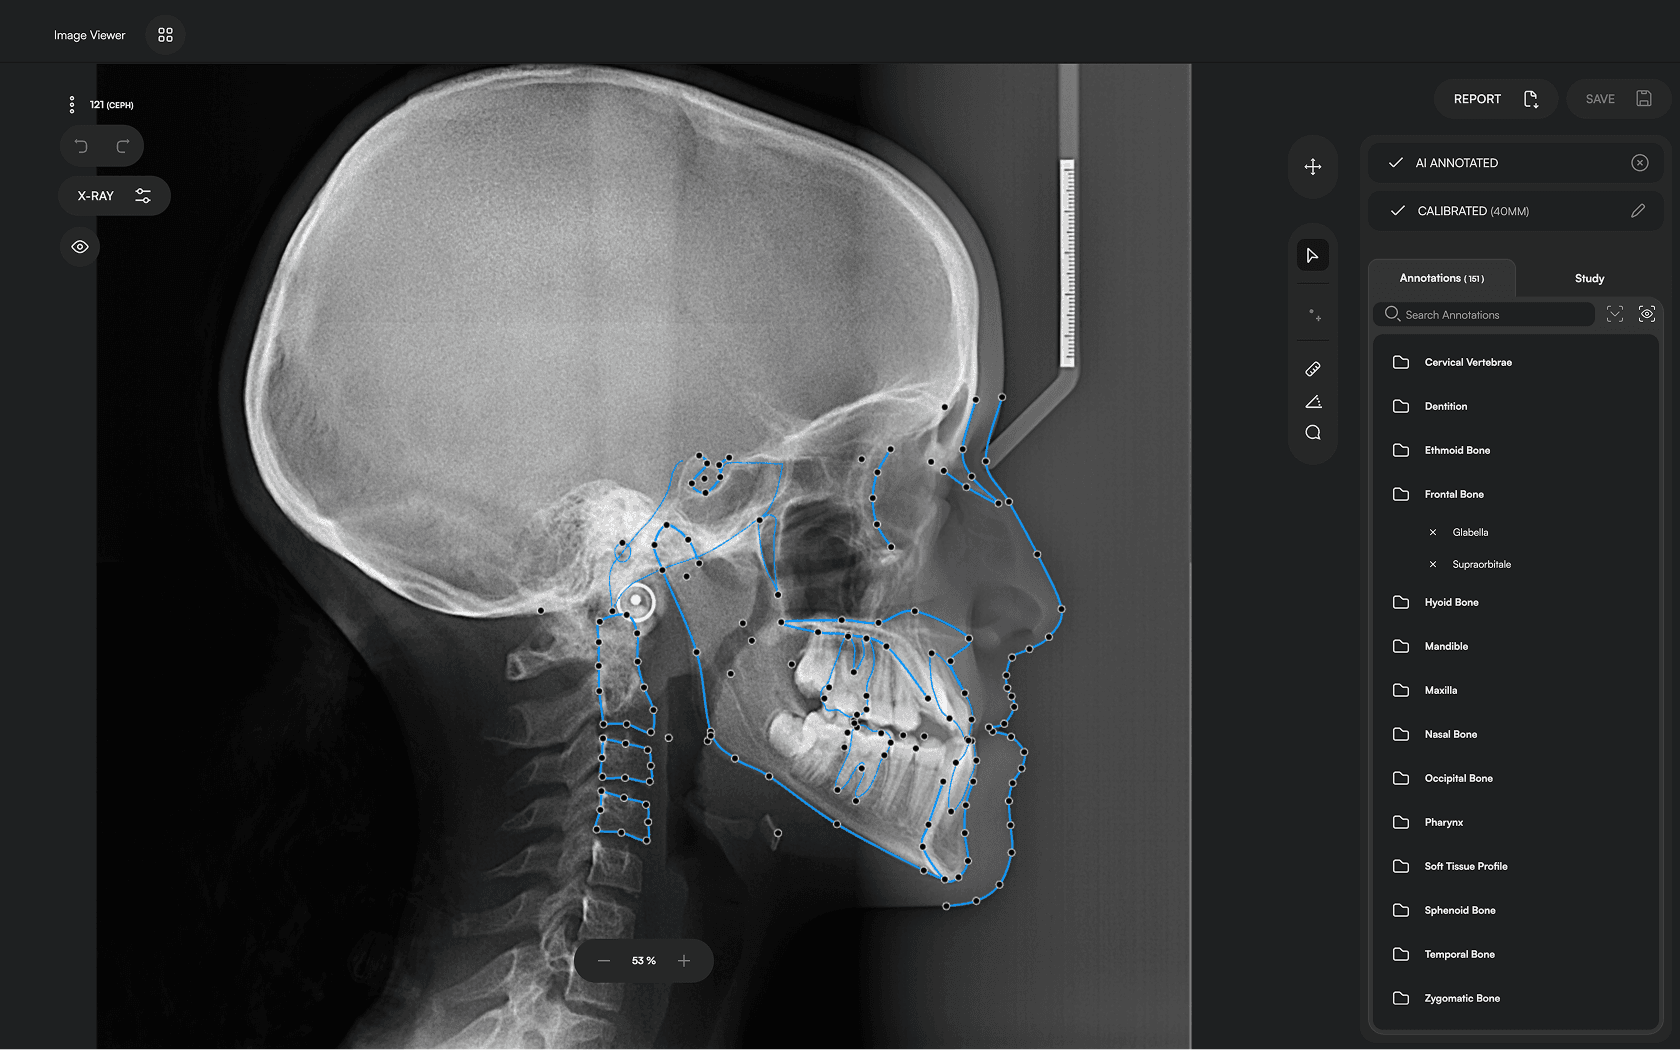

150+ landmarks traced in seconds

Identify 150+ orthodontic landmarks in under 10 seconds — a task that

traditionally may take more than 30 minutes.